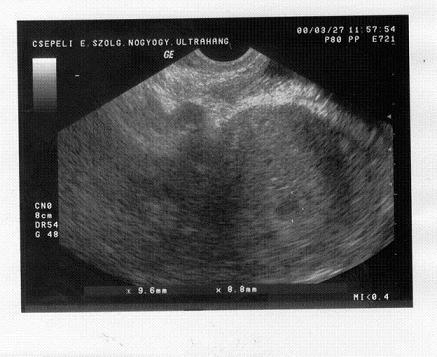

A fenti fekete foltocska micsoda?